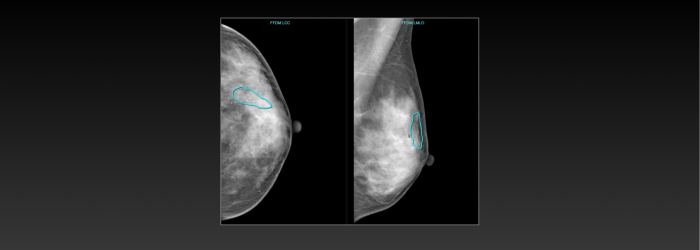

联影智能FFDM乳腺智能分析系统可辅助医生评估乳腺腺体分型及乳房内病灶的检出,包括乳腺常见的四大病灶:肿块、钙化、结构扭曲和不对称;同时系统提供病灶BI-RADS分类、定位等多维分析结果,自动生成图文报告,提升医生的阅片和工作效率,优化乳腺癌诊断流程,关爱女性健康。

基于AI技术,联影智能FFDM乳腺智能分析系统可对乳腺X线图像进行腺体分型、病灶检测及定位、多维分析病灶,避免不同医生阅片的主观差异,实现同质化水平,同时还能减轻医生阅片压力。